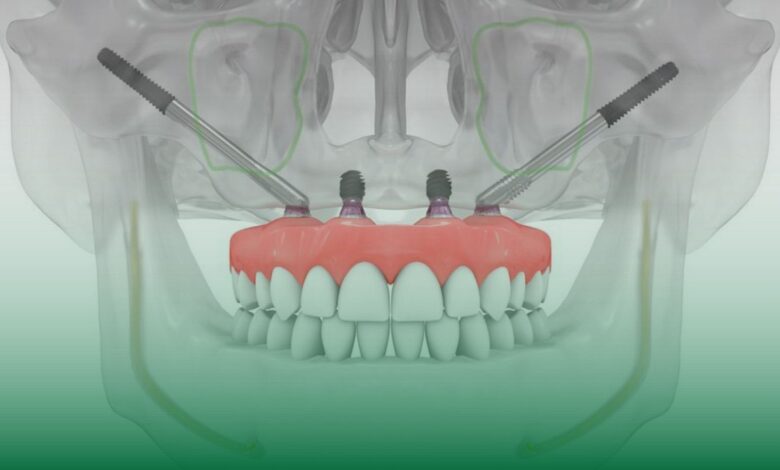

Zigomatik implantlar, geleneksel dental implantlardan farklı olarak, üst çenedeki kemik yetersizliği durumlarında elmacık kemiği (zigomatik kemik) üzerine yerleştirilen özel implantlar. Bu yöntemin özellikle ileri derecede kemik kaybı yaşayan hastalar için geliştirilmiş bir çözüm sunduğunu belirten Dr. Öğr. Üyesi Musa Erdem, “Zigomatik kemik, üst çenenin daha üst bölgesinde yer alan ve güçlü bir yapıya sahip olan bir kemiktir. Üst çenedeki kemik kaybı nedeniyle normal implantların uygulanamadığı hastalarda, zigomatik implantlar kalıcı bir çözüm sunar” dedi.

Dr. Öğr. Üyesi Musa Erdem’e göre zigomatik implantlar, klasik dental implantlardan farklı olarak daha uzun yapıdadır. Geleneksel dental implantlar çene kemiğine yerleştirilirken, zigomatik implantlar doğrudan zigomatik kemiğe uygulanır. Bu yöntemin en büyük avantajı, ileri kemik kaybı olan hastalarda bile implant tedavisine olanak sağlamasıdır.

- “Dental implantlar genellikle diş çekiminden sonra çene kemiğine yerleştirilir. Ancak üst çenede yeterli kemik olmadığı durumlarda geleneksel implantlar uygulanamaz. Zigomatik implantlar, üst çenedeki kemiğin yetersiz olduğu durumlarda elmacık kemiğine sabitlenerek diş protezi için güçlü bir dayanak noktası oluşturur.”

- “Zigomatik implantlar, boyut açısından geleneksel dental implantlardan daha uzundur. Normal dental implantlar 8-14 mm uzunluğunda olurken, zigomatik implantlar 30-55 mm uzunluğunda olabilir.”

Zigomatik İmplant Uygulaması Nasıl Yapılır?

Zigomatik implant cerrahisi, geleneksel implant uygulamalarına kıyasla daha teknik bir hassasiyet gerektirir. Bu nedenle, işlem genel anestezi altında veya derin sedasyon yöntemiyle gerçekleştirilir. Uygulama süreci hakkında bilgi veren Dr. Öğr. Üyesi Musa Erdem şunları söyledi:

“Zigomatik implant uygulaması cerrahi bir işlem gerektirir ve genellikle genel anestezi altında yapılır. Bazen derin sedasyon yöntemi de tercih edilebilir. İşlem sırasında, implantlar elmacık kemiğine sabitlenir ve diş protezine sağlam bir dayanak oluşturur. Hastalar operasyon sonrası uyandıklarında genellikle ağrı hissetmezler. Uygulanan ilaçlar sayesinde rahat bir iyileşme süreci geçirirler.”